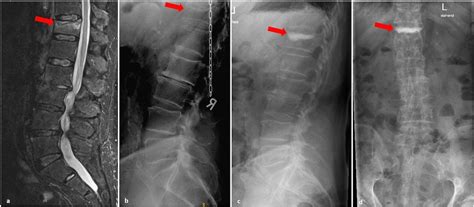

So, how do doctors actually diagnose an Ideckplattenfraktur LWK 1? Usually, it starts with a thorough physical exam and a review of the patient’s medical history. The doctor will ask about the mechanism of injury – how did the fracture occur? They’ll also assess the patient’s symptoms, such as the location and severity of pain, any neurological deficits, and any other associated injuries. Imaging studies are essential for confirming the diagnosis and determining the extent of the fracture. X-rays are often the first-line imaging test, as they can quickly and easily visualize the bones of the spine. However, X-rays may not always be sensitive enough to detect subtle endplate fractures. In these cases, a CT scan or MRI may be necessary. A CT scan provides more detailed images of the bony structures of the spine, while an MRI can visualize the soft tissues, such as the spinal cord, nerves, and ligaments. This is particularly helpful in identifying any nerve compression or other soft tissue injuries.